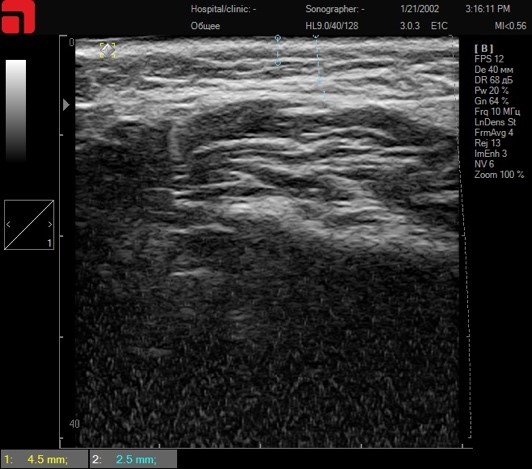

Рис. 1. Строение кожи, подкожно-жировой клетчатки и SMAS в щечной области.

Соединительная ткань при сканировании кожи представлена структурами высокой эхогенности (белый цвет на сканограмме) в гиподерме и на SMAS. На данном снимке, сделанном на аппарате Doublo, мы видим (сверху-вниз) собственно кожу (эпидермис и дерма), под ними подкожно-жировую клетчатку с множественными трабекулами и перемычками соединительной ткани (см. замер 2,5 мм), а далее непосредственно SMAS-слой, начинающийся у данного пациента на глубине 4,5 мм. Каждый пункт сканирования несет в себе значимость для эффективной и безопасной работы. Рассмотрим основные точки сканирования и данные, которые можно из них извлечь, а также составим протокол процедуры.